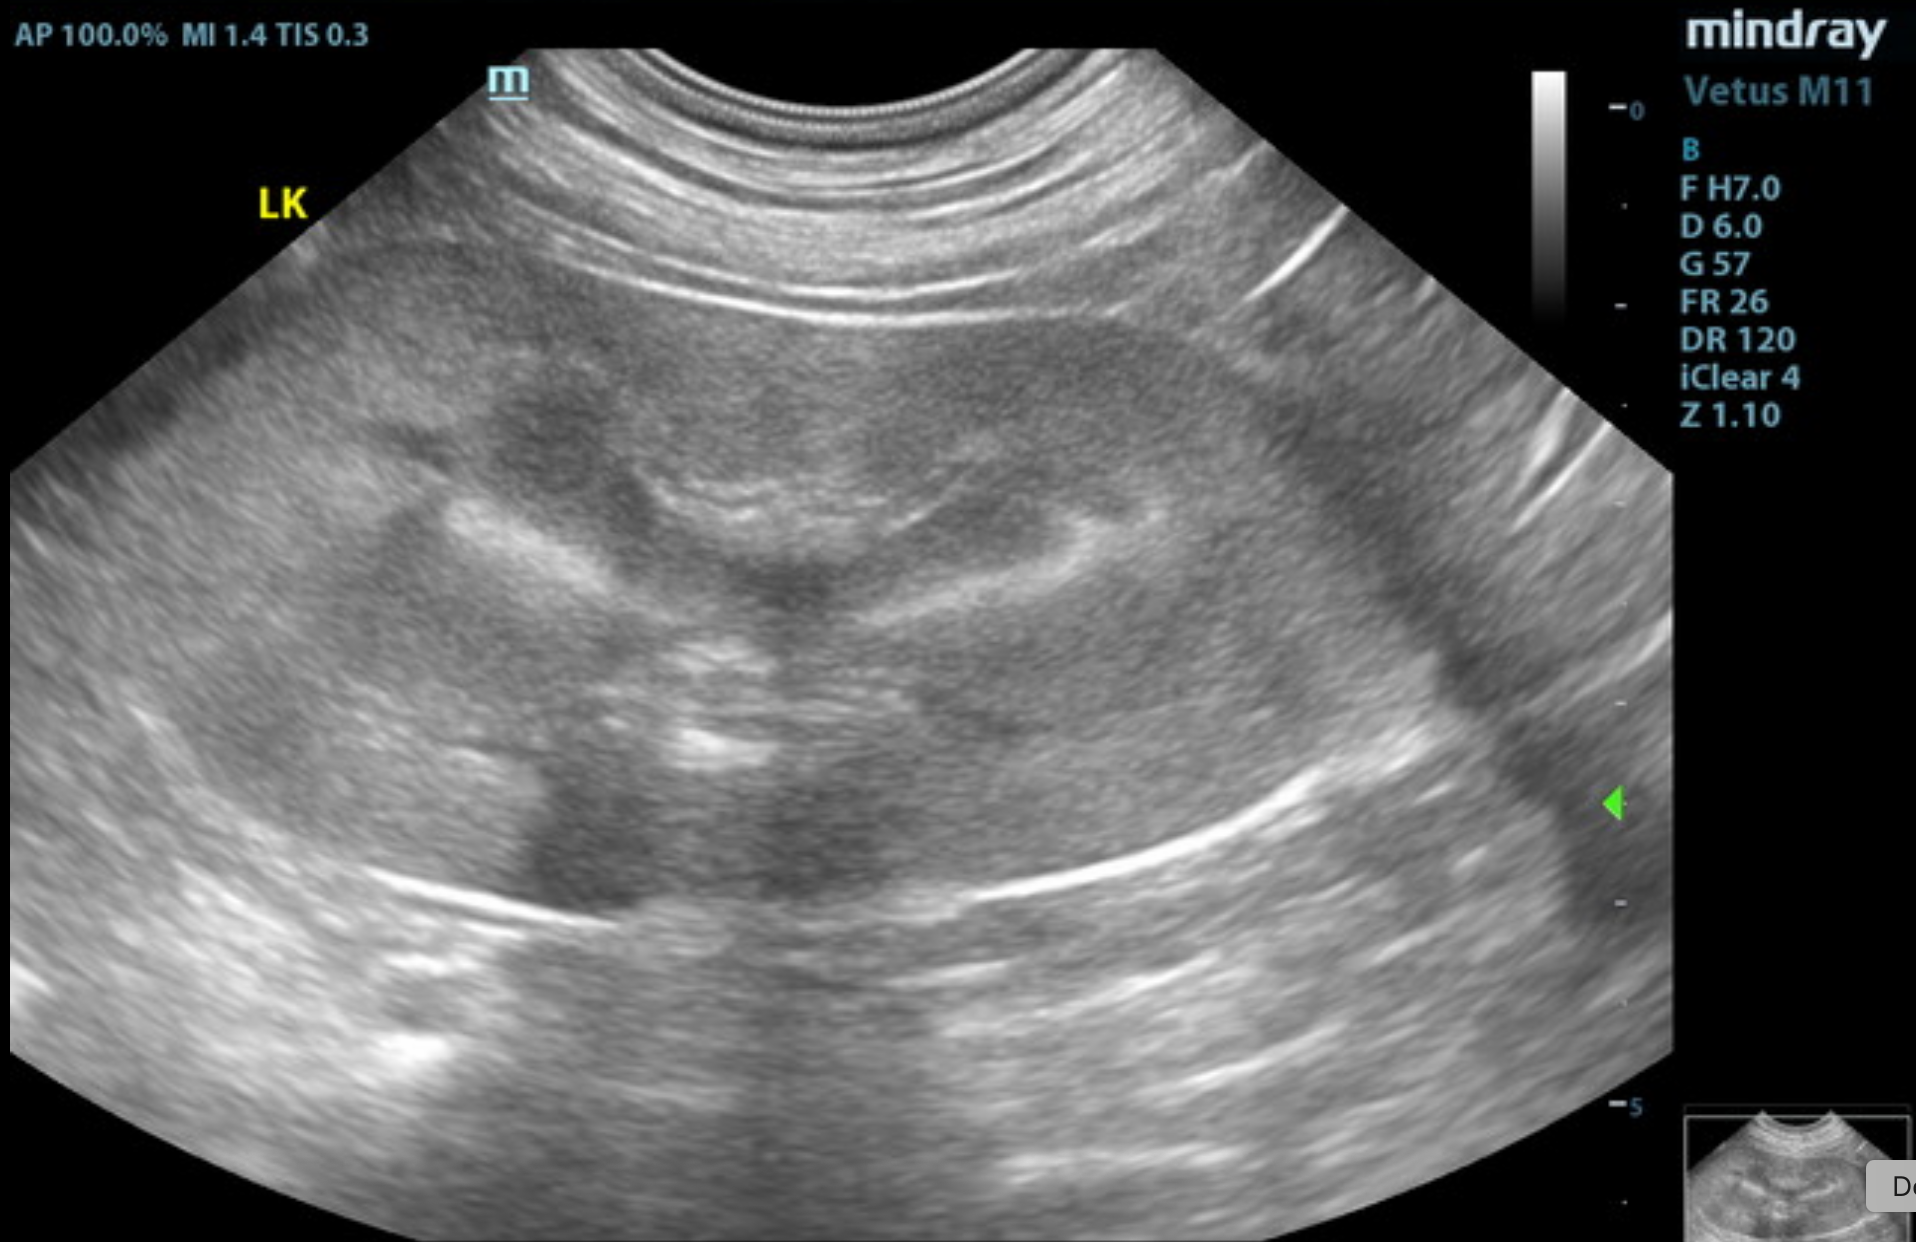

The kidneys revealed largely normal size and structure. Corticomedullary definition and ratio (cortex 1/3 of medulla) were essentially maintained with some age-related loss of curvilinear patterns regarding the capsule and C/M junction. The cortices presented largely uniform texture with some increased echogenicity expected for this age patient. Medullary structure differed distinctly from that of the cortex and no evidence of pelvic dilation was present. The right kidney measured 5.6 cm. The left kidney measured 6.6 cm.